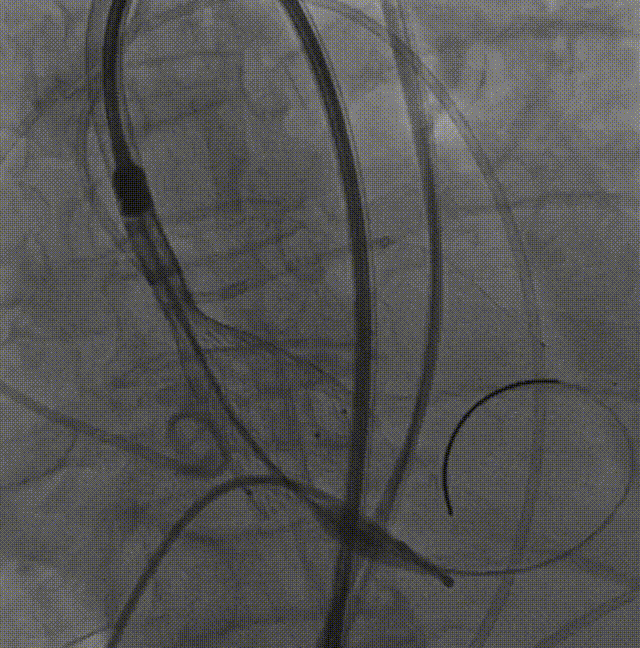

LM烟囱支架植入4.0*30mm